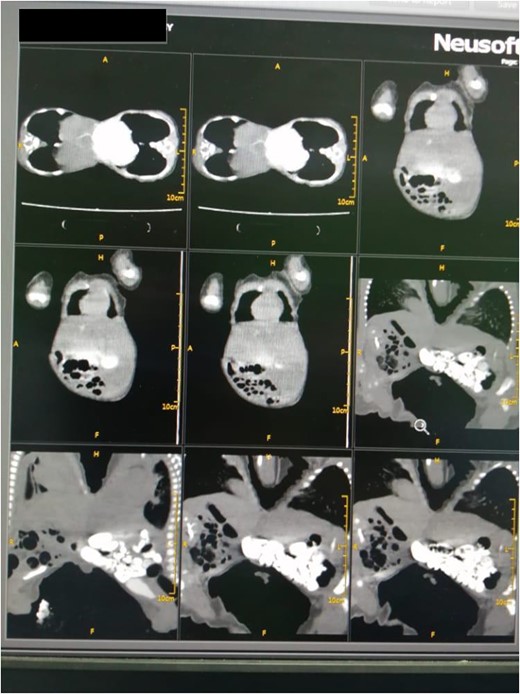

A computed tomography scan revealed ventral omphalopagus-xiphoid union of conjoined twins with separate vital organs and signs of fusion of the anterior aspect of the livers (adhesion), as well as one lower limb arteriovenous malformation (AVM) (AV fistula) seen extending from external iliac major vessels in both with difference in affected side (Fig. 3). Both twins’ echocardiography scans were completely normal. Both the complete blood count and the liver function test were normal.

CT scan with contrast of case 2 showed omphalopagus type of conjoined twins with fusion of anterior aspect of the livers and separate other vital organs.